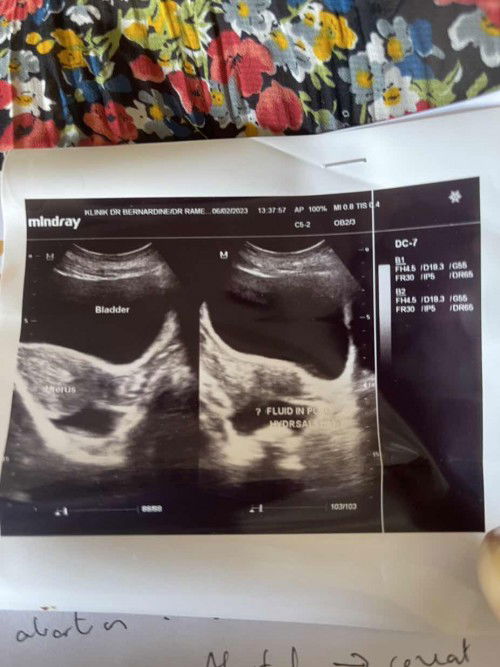

salam ibu2 semua. bulan 11 lalu saya keguguran tak cuci just tunggu keluar habis. then 12 saya period ,period panjang rupanya tak habis keluar 27.12 Doc bagi ubat bersihkan. alhamdulillah 1minggu dah bersih. 1.2.23 test upt 3hari berturut alhamdulillah positive. 6.2.23 scan doc bagitau hanya nampak fluid tak da yang lain. doc takut kandungan luar rahim, Doc ada sediakan surat jika ada sakit terus pergi kecemasan. dup dap dup dap tunggu appointment doc jumaat ni untuk scan. Mohoh doa dari rakan2 semua semoga semua baik2 saja, insyaallah ada reseki mengandung lagi. aamiin❤️